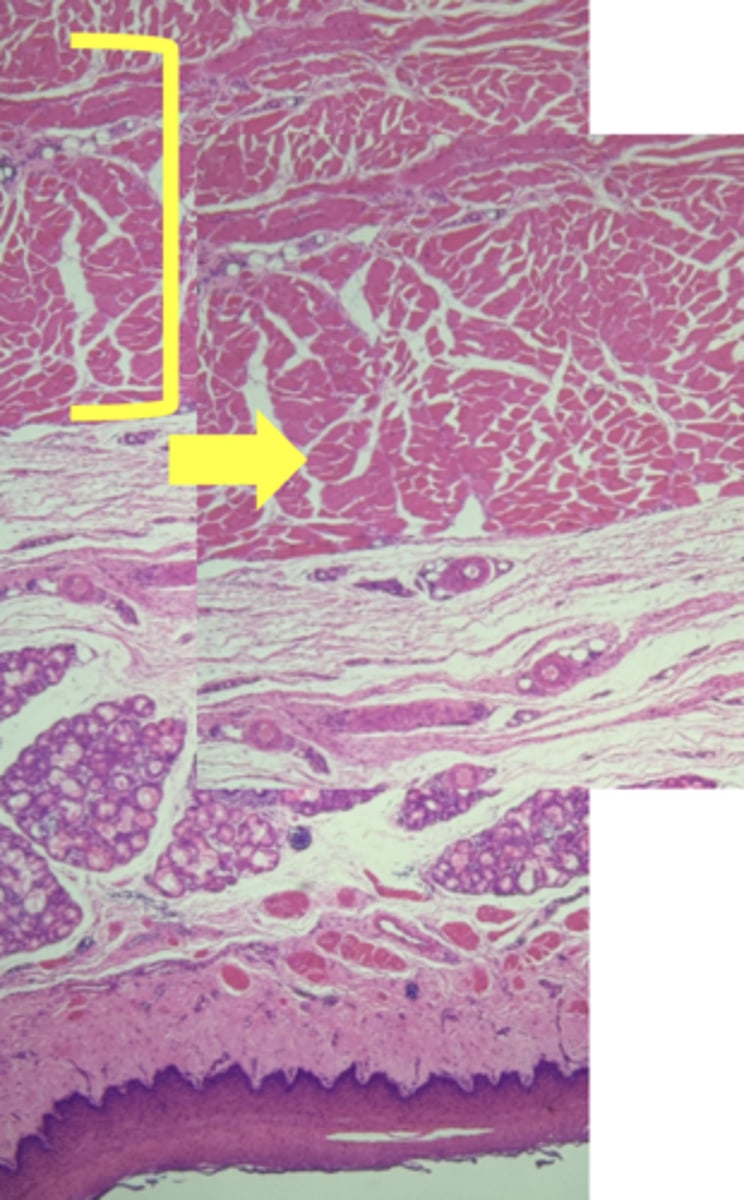

Esophagus

name the tissue

Mucosa

(esophagus)

Submucosa

muscularis externa

stratified squamous epithilium (KEY CHARACTERISTIC)

lamina propria

muscularis mucosae

circular layer

longitudinal layer

A- Esophagus

B- Stomach

Name the Tissue A & B

stomach